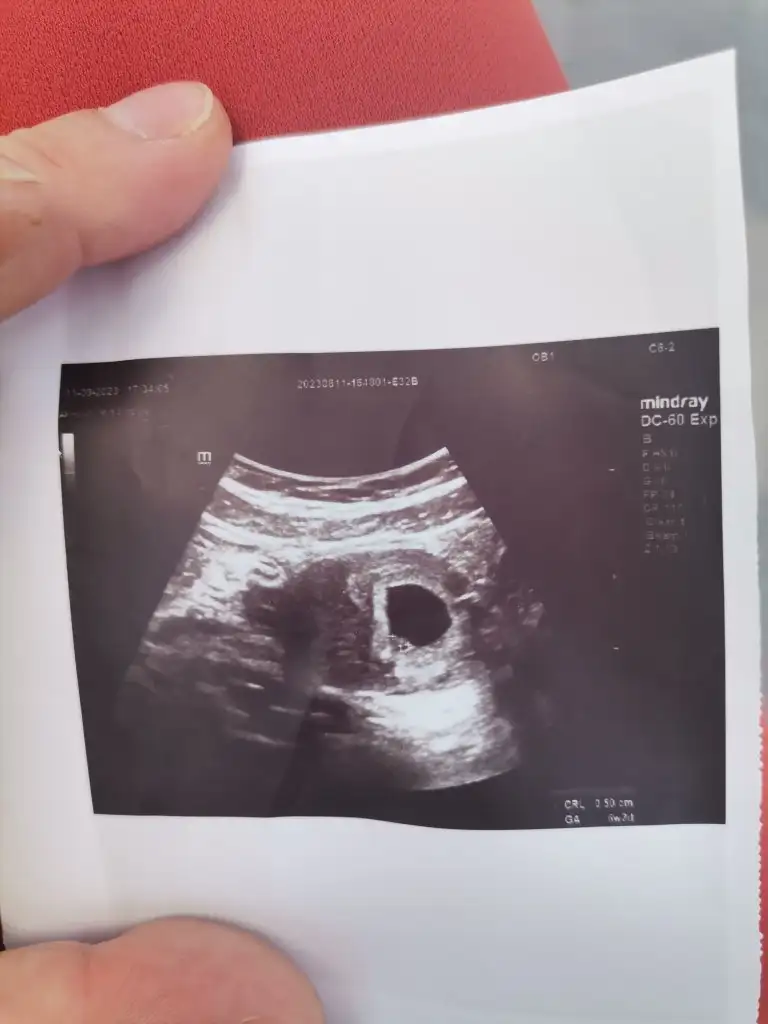

Kızlar Ramzi teorisinden anlayan biri bakabilir mi cinsiyeti ne olabilir?? Bu arada, hepimiz biliyoruzki bilimsel bir gerçekliği yok vesaire ama bizin işin heyecanındayız o yüzden kimse üstümüze gelmesin lütfen 💓🫶🏻

Benimkinide yorumlarmsnz. Sadece tahmin. Benim için ilk saglik ztn

Benimkinide yorumlarmsnz. Sadece tahmin. Benim için ilk saglik ztn. 6+4 de fotografi